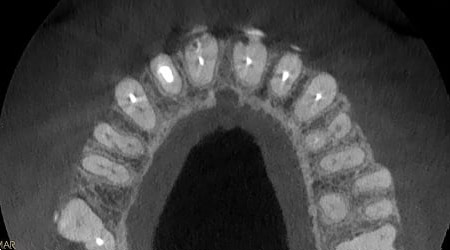

ESTADO DE LA BOCA

Las imágenes de muy alta resolución (hasta 75 micras) resultan idóneas para las necesidades de endodoncia. El sistema CS 9600 incluso proporciona la capacidad de capturar exploraciones de boca completa a la máxima resolución.